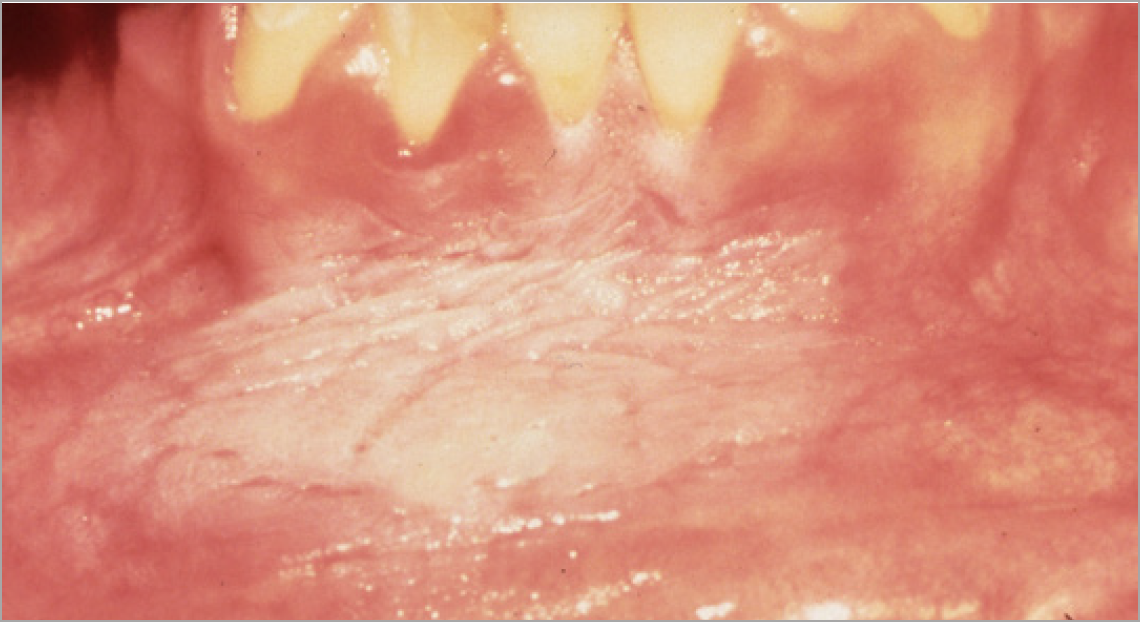

Figure 2. Example of Oral Cancer - courtesy of dentalcare.com

Figure 2

Patients typically present with a sore throat, ear pain, painful swallowing, or hoarseness, and on physical exam they often have lymph node involvement in the neck. The highest risk sites are at the base of the tongue and the tonsillar area. Palpation of the neck has never been more important. The highest frequency of HPV-positive cancer is related to oral sex and to the number of partners. Figure 2 shows an example of cancer, found on the buccal mucosa.